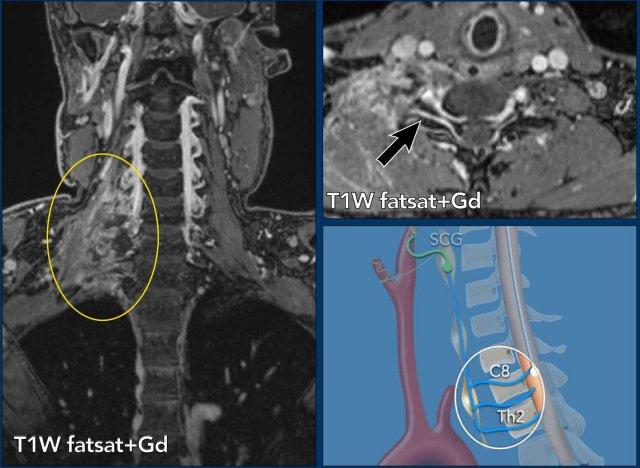

Những hình ảnh này của một người đàn ông 78 tuổi

được biết là có ung thư biểu mô tế bào vảy ở sàn miệng và than phiền về nhìn đôi.

Khi khám thực thể, bệnh nhân mất định hướng và có

rối loạn vận ngôn và hội chứng Horner.

Dựa trên những phát hiện này, chúng tôi cho rằng hội chứng Horner là

do nguyên nhân trung ương.

Hình ảnh

T1 MPRAGE 3D cho thấy một tổn thương ngấm thuốc dạng vòng nhẫn lớn ở vùng đồi thị bên phải và một tổn thương thứ hai ở bán cầu não phải.

Kết luận

Di căn của ung thư biểu mô tế bào vảy.

Thông thường các ung thư biểu mô này không di căn dễ dàng như vậy.

Ở các tầng khác có nhiều di căn hơn (vòng tròn).

Hình minh họa cho thấy mức độ của bệnh lý.